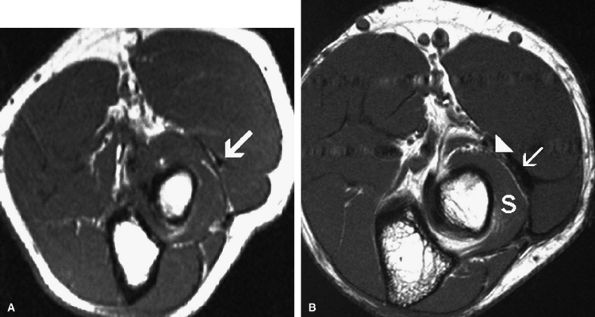

FIGURE 12.33 ● Free edge of the thickened extensor carpi radialis brevis. (A) Axial T1-weighted image depicts a low-signal free edge of the extensor carpi radialis brevis in an asymptomatic individual. (B) The thickened free edge (arrow) is shown in close proximity to the posterior interosseous nerve (arrowhead) in a patient with radial tunnel syndrome. Associated mild fatty infiltration of the supinator muscle (S) is noted.

|

FIGURE 12.34 ● Posterior interosseous nerve syndrome secondary to bicipitoradial bursitis. (A) Axial PD-weighted image shows a markedly distended bicipital radial bursa (arrows) adjacent to the posterior interosseous nerve (arrowhead). (B) Axial fat-suppressed T2-weighted image demonstrates denervation edema and mild atrophy of the supinator (s), extensor carpi ulnaris (ecu), and extensor digitorum communis (edc) muscles in the proximal forearm.